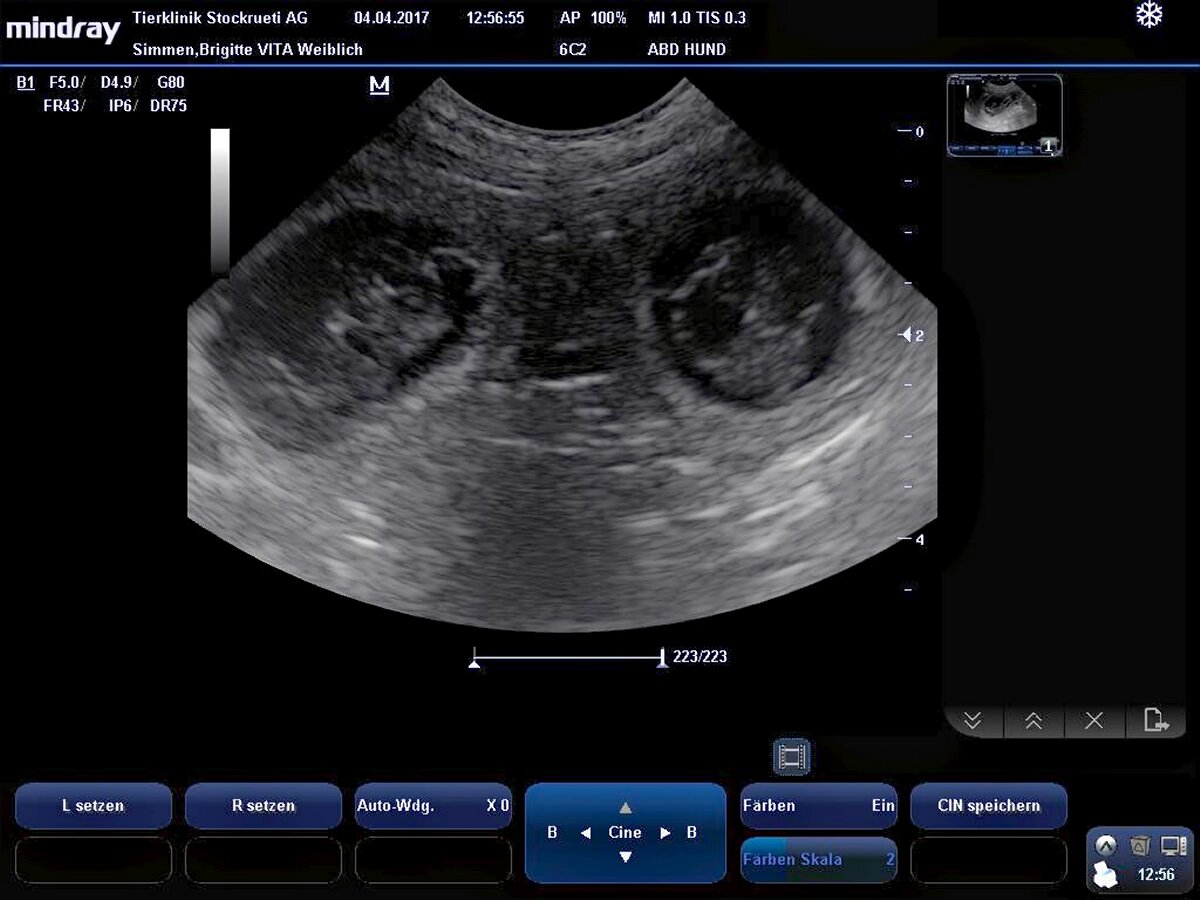

Nach dem heutigen Ultraschall ist Vita definitiv trächtig! Nun haben wir bereits Halbzeit - in ca 4 1/2 Wochen sollte der R-Wurf zur Welt kommen!